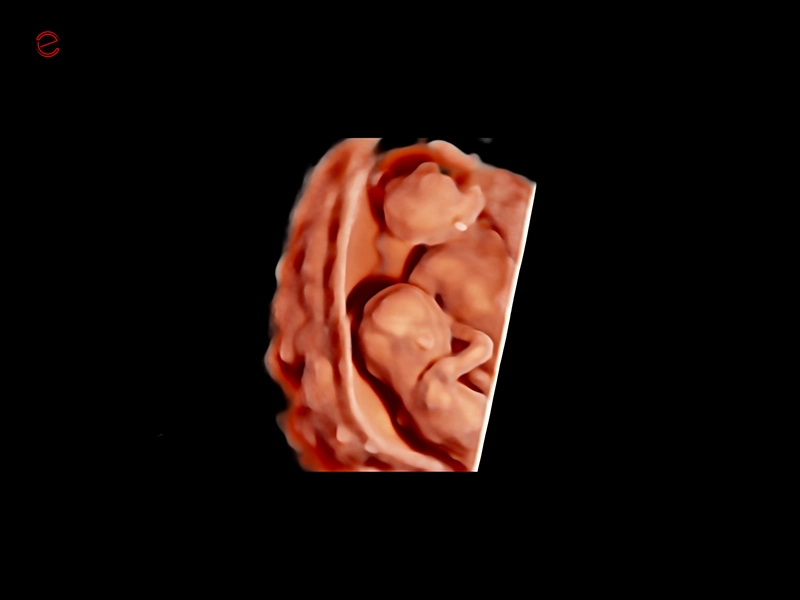

MyLab™9 Platform - Baby Face rendering in real-time with XLight

MyLab™9 Platform - Baby Face rendering in real-time with XLight